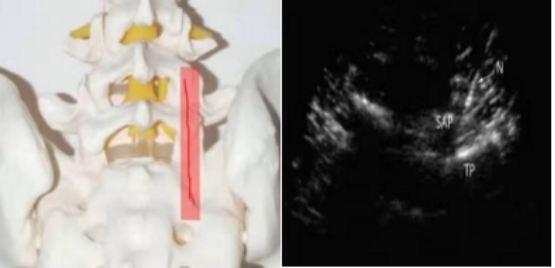

3、超声在外周神经的应用:肌骨超声对于神经的评估分辨率高,可清晰显示外周神经的神经束、神经束膜、神经外膜结构、神经粗细以及与周围组织的关系,准确诊断周围神经炎及外周神经损伤的原因、部位。主要扫查的外周神经包括:上肢的臂丛神经、正中神经、桡神经、尺神经;下肢的股神经、坐骨神经、胫神经、腓总神经、股外侧皮神经。常见疾病:神经损伤、神经卡压、神经炎、周围神经源性肿瘤等。

图3 腕管综合征